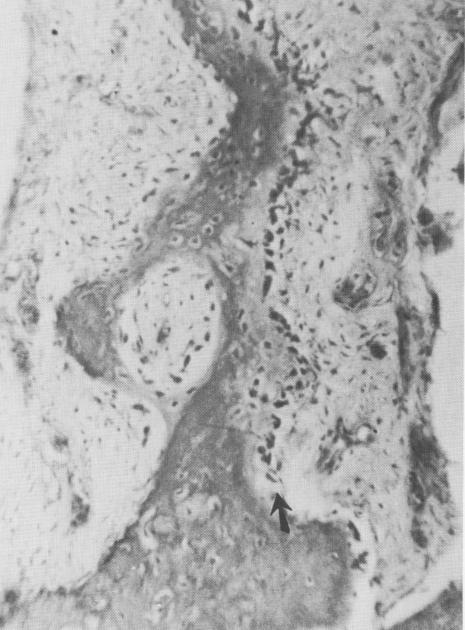

Fig. 4-78. When the hole was placed near the alveolar crest, the osseous bridge underwent an inflammatory breakdown (arrow). (Courtesy M. Hodosh.)

2 Inflammation of bone tissue when crystalline implant at alveolar crest